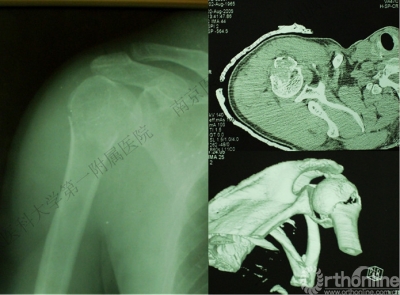

病例3

男性,27岁,车祸致右肩部肿痛、活动受限6小时。

术后肩关节X线片

1.X线片

2.肩关节CT

确定肩关节后脱位。

了解反Hill-sachs损伤和程度。

观察肱骨近端主要骨折线和次要骨折线及形态。